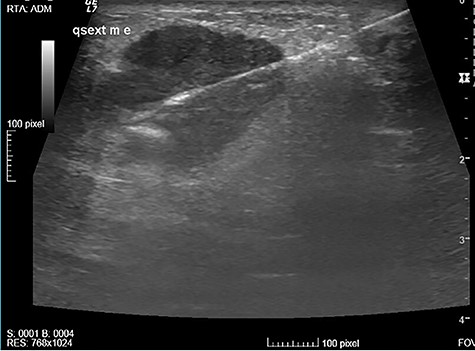

The authors report the case of a 73-year-old female patient with complaints of a left breast lump, referred to our Breast Clinic, due to a suspicious nodule of 25 mm in the upper external quadrant (UEQ) of the left breast, without suspicious axillary lymph nodes on breast ultrasound (US) (Fig. 1) and mammogram. Menarche and menopause occurred at 10 and 51 years old, respectively. Her menstrual cycles had been regular. She had had three gestations and three normal deliveries after which she breastfed. She had taken oral contraceptives but no hormone replacement therapy. She had a history of alcohol consumption and had no relevant family history. At our clinic, upon examination, she had a suspicious lump of around 30 mm in the UEQ of the left breast. The breast micro-biopsy revealed a breast tumor with abundant chondroid stroma component with necrotic areas; cells were small with an increased nucleus-to-cytoplasm ratio, hyperchromatic nuclei, positioned in a cordonal pattern (probable metaplastic carcinoma). Concerning immunohistochemistry, it was positive for AE1/AE3 and negative for BCL2, CD34 and P63. This case was presented at our Multidisciplinary Breast Tumour Board and surgery was proposed. Thus, she underwent a breast conservative surgery (BCS) (wire-guided quadrantectomy) (Fig. 2) and axillary sentinel lymph node dissection (SLND) (following de Z0011 protocol), which ran uneventfully. Intra-operative frozen section revealed negative microscopic surgical margins and three axillary lymph nodes negative for macro-metastasis. Metallic clips (of titanium) were applied in the margins of the quadrantectomy. She had an uneventful recovery and was discharged home on the third post-operative (PO) day. The definite pathological report (Fig. 3) revealed an invasive breast carcinoma, of metaplastic type, with mesenchymal differentiation (chondroid), intermediate (2) grade, triple-negative, with 31-mm, negative microscopic surgical margins and three axillary lymph nodes negative for metastasis, pT2N0 (sn). The tumoral lesion was a proliferation with infiltrative margins, presenting a peripherical component of trabecular and cordonal pattern, composed by small cells with ill-defined margins and hyperchromatic nuclei. Pleomorphism was moderate, exhibiting relatively frequent mitosis’ figures. It exhibited transition to a matrix of chondroid features, centrally positioned, abundant, with features of maturity. Peripherally, there were no tumoral veno-lymphatic emboli, images of peri-neuronal infiltration nor necrotic areas, but there was a component of in situ carcinoma. Concerning immunohistochemistry, it was positive for vimentin, CK 5/6 and 7, p63 and GATA3, but negative for smooth muscle actin, calponin, CK 20, S100 protein, hormonal (estrogen and progesterone) receptors and human epidermal growth factor receptor 2 (HER2). The proliferative index, assessed by the Ki67, was of 80% on the trabecular component. She had a thoracic, abdominal and pelvic computed tomography done, which did not show any additional disease. This case was presented again at our Multidisciplinary Tumour Board, where chemoradiotherapy was proposed. The chemotherapy protocol proposed was 4 cycles of doxorubicin 96 mg and cyclophosphamide 965 mg each 21 days, followed by 12 cycles of weekly taxane.

Suspicious nodule of 25 mm, in the UEQ of the left breast on breast US.